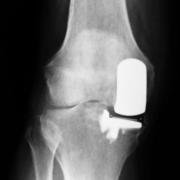

Once the joint damage extends beyond a single compartment, there is generally little to be gained by doing a uni-compartmental procedure. One is then looking at total knee replacement, which in effect means replacing both tibio-femoral joints and possibly the patellofemoral joint as well. In a total knee replacement (TKR) the end of the long bones of the knee joint (thighbone or femur and shinbone or tibia) are sawn off with special jigs, and the bits replaced with artifical materials. The prosthesis may be cemented onto the bone, or may rely on special coatings to fuse to the bone. The femur bit is usually replaced with metal (eg. titanium or zirconium), while the tibia bit is usually plastic or metal and plastic. The procedure is also often referred to as an 'arthroplasty'.

The femoral part of joint replacement is usually metal, curved into the shape of the lower end of the femur with its two condyles (the 'knuckles'). Usually the metal is titanium-based, but other metals (eg zirconium) are used as well as mixtures. Ceramic is being tried by a small number of manufacturers, as it reduces the wear of the polyethlylene component upon which the femoral part rides.

The tibio-femoral unicompartmental prosthesis has two components - the curved metal femoral component shaped much like the femoral condyle it replaces, and the almost flat tibial component - made of polyethylene - replacing the flat tibial plateau. This latter may be fixed to a metal backing plate or it may move freely on it.

The total knee prosthesis - like its cousin - has a metal femoral component, this time with two rounded condyles, sitting on a flattened polyethylene tibial surface, again fixed or free on a metal backing plate

The important thing to understand is that the condyle and underlying tibia are incongrous - one is rounded, while the other is flattened. Early designs had metal on both the femoral and tibial side, but there were major problems with wear - and the tibial contact surface was replaced with polyethylene. Where a flatter polyethylene plate was used, greater mobility was possible for the patient, but the wear of the polyethylene was greater. Constraining the femoral condyles in grooves within the polyethylene created less wear of the polyethylene, but reduced the patient's mobility, as the joint operated effectively like a hinge joint.